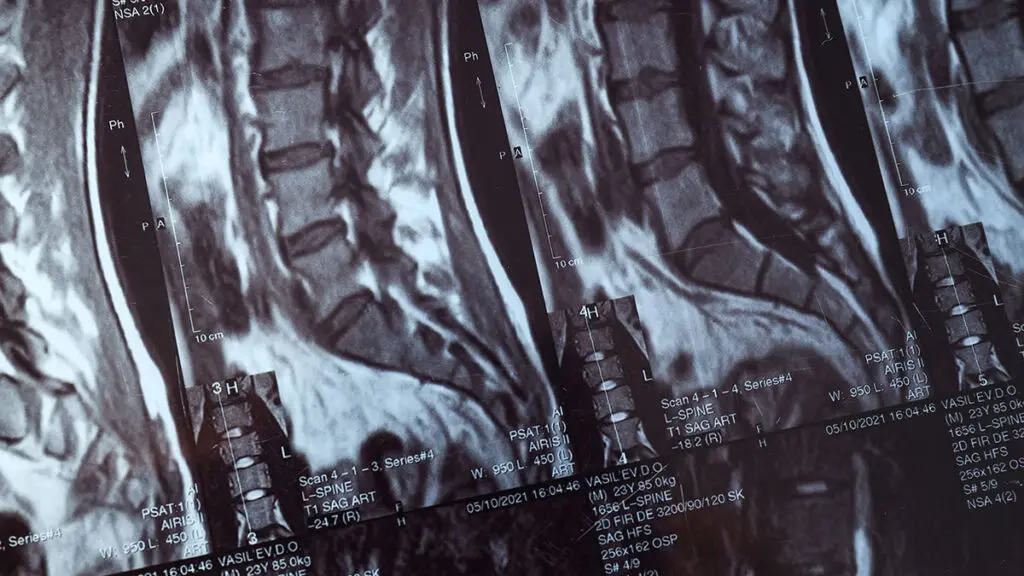

Il trattamento di operazione stenosi vertebrale viene pianificato sulla base di una valutazione diagnostica completa (RMN, TAC, esame neurologico) e adattato alle specifiche esigenze di ogni paziente. L'obiettivo è alleviare la compressione nervosa, migliorare la qualità della vita e prevenire danni neurologici permanenti, con il minimo impatto chirurgico possibile.